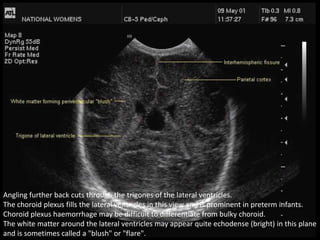

Angling further back cuts through the trigones of the lateral ventricles.

The choroid plexus fills the lateral ventricles in this view and is prominent in preterm infants.

Choroid plexus haemorrhage may be difficult to differentiate from bulky choroid.

The white matter around the lateral ventricles may appear quite echodense (bright) in this plane

and is sometimes called a "blush" or "flare".